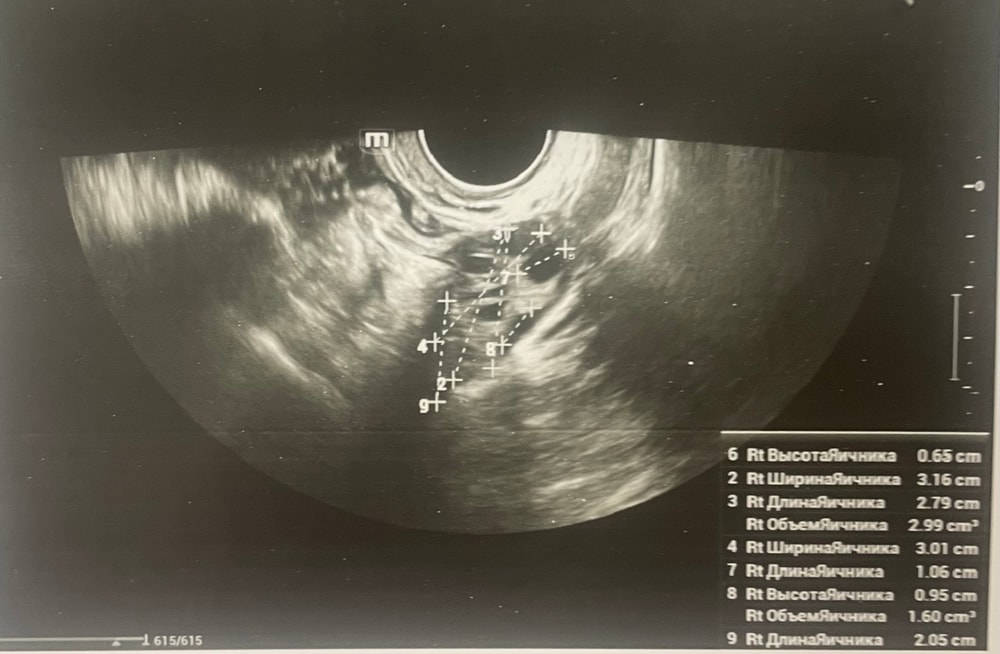

Ждем дня Х/тесты/признаки БДобрый день, мы с мужем планируем беременность и в этом месяце произошло что то странное… дата начала последней менструации 4 октября закончилась 8, овуляцию отслеживала всю неделю почти сначала были бледные еле заметные полоски, 23 октября жирные четкие полоски, 24 октября стала чуть бледнее но яркая, вообщем положительный ещё был, с 25 числа тест уже отрицательный, через день после овуляции 26 числа стала странно себя чувствовать и во время овуляции болел живот то справа то с лева и поясница, так через день после начали болеть соски грудь вообще не болела, живот то болит то нет и с поясницей также, позже появилась небольшая изжога, нога немеет правая не знаю с чем связано), все это началось за 2 недели до месячных в середине цикла скажем так 29 числа пошла на узи спустя 6 дней грубо говоря гиня сказала что у меня была очень хорошая овуляция, что её признаки сохраняются до сих пор так скажем, желтое тело СПРАВО 20 мм, мои симптомы и все это очень похоже на беременность сказали большая вероятность, я очень была рада и надеялась, после узи появились выделения с комочками, до этого были просто густые белые выделения, утром тоже самое, пошла опять к гинекологу она сказала это может быть при ранец беременности сказала какие свечи купить, вечером я попала в не большое ДТП, удар был в поясницу и копчик, живот начал тянуть и поясница сильно болеть, начала болеть сама грудь помимо сосков, живот прошел относительно быстро, а вот поясница ломит до сих пор, решила сходить ещё раз на узи очень испугалась, на узи я пошла 31 через два дня после предыдущего и уже к другому гинекологу, моя на больничном, она сказала, что у меня отсутствуют даже косвенные признаки беременности и желтое тело с ЛЕВО А НЕ С ПРАВО, я не понимаю как такое может быть, очень расстроилась и совсем забыла про фото узи, она мне его не дала только заключение и как выяснилось уже не дадут оно не сохранилось, сказали переделывать, я очень доверяю своему гинекологу, но по заключению второго врача о беременности не может быть и речи в этом цикле, я не понимаю как желтое тело оказалось с лево если оно точно было справа в этом я уверена, а вторая врач уверяет во Братном, живот в обуляцию хоть и болел с двух сторон но больше справа помойму, вообщем я не понимаю есть ли шанс что я беременна или все таки нет, я понимаю что это слишком рано, до задержки ещё 4 дня, но мне плохо уже неделю по симптомам даже больше это же не просто так, я прикреплю фото заключения, могу ли я быть беременна, если посмотреть на эти заключения хотябы, подскажите пожалуйста фото узи относятся к 29.10, без фото 31.10